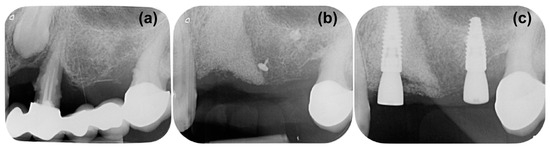

Periapical X-ray (Figure 1a) showed periapical bone loss to the first premolar (24), which appears to have been treated endodontically in an incongruous way. The second molar (27) showed a mesial bone defect. The X-ray also showed the presence of an impacted canine (23) with increased peri-coronal space, indicating a possible bacterial contamination. In order to evaluate the impacted canine and set the treatment plan, cone beam computed tomography (CBCT) was executed (Figure 1b,c). The CBCT examination highlighted an area of radiotransparency for the impacted canine and the complete loss of bone support for tooth 24. It also highlighted an alteration in the shape of the apex of the canine in contact with the maxillary sinus.

Figure 1. (a) Initial X-ray demonstrating peripheral bone loss to the first premolar 24. (b,c) cone beam computed tomography (CBCT) demonstrating severe bone loss around 24 and the positioning of the impacted canine 23.